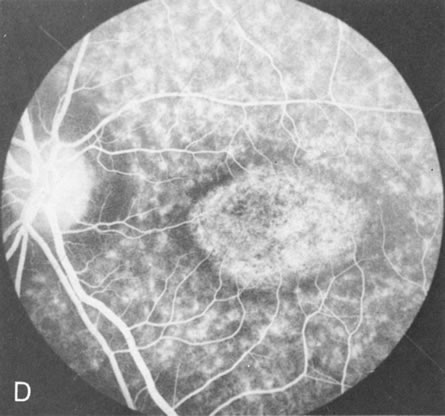

In Stargardt's disease, thes most common hereditary macular dystrophy, FA has a variety of functions. In the mildest fundus presentation, with visual symptoms and visual function out of proportion to the observed maculopathy, FA can confirm or even make the diagnosis and can avoid a mistaken diagnosis of malingering, hysteria, or central nervous system disease (Fig. 9A and B). When a maculopathy is present without surrounding parafoval flecks, FA may show patchy areas of transmission hyperfluorescence in the posterior pole, indicating a more diffuse involvement (Fig. 9C and D).

Fig. 9. Stargardt's disease–fundus flavimaculatus. The mild maculopathy (without parafoveal flecks) (A) is confirmed by the angiogram (B). The relative absence of the underlying choroidal flush, resulting in an easier visualization of the overlying retinal capillary circulation, has been referred to as the “silent” or “dark” choroid, and is considered a common finding in this disease. The diagnosis is confirmed in an individual with a pigmentary maculopathy without flecks (C). Here the angiogram demonstrates widespread transmission hyperfluorescence and a “silent” or “dark” peripapillary area (D). When the posterior pole shows multiple yellowish-white flecks (E), the angiographic findings do not necessarily correspond to the flecks (F). It should also be noted that despite the widespread abnormalities, the background choroidal fluorescence is normal.

In a large majority of patients (86% in one study),20 there is an absence or decrease in the background choroidal fluorescence (which is referred to as the “silent” or “dark” choroid) (see Fig. 9B). This warrants special attention because it occurs so frequently, is rarely found in other retinal disorders,21 and may be related to histopathology that shows an increase in lipofuscin in the RPE.22